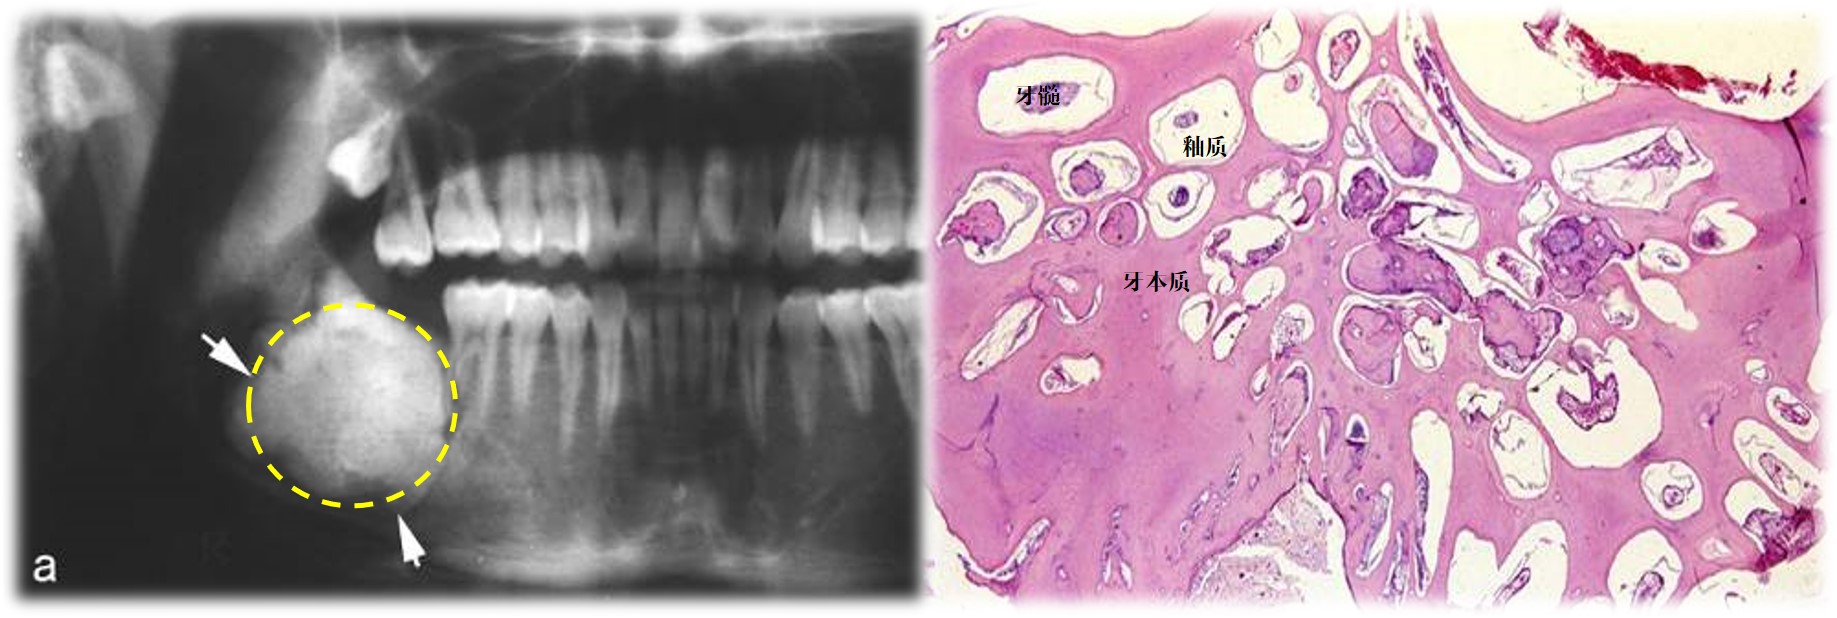

2)混合性牙瘤

临床:多见儿童和青年,好发部位为下颌前磨牙区和磨牙区。

X线:境界清楚的放射透光区,可见放射阻射性结节状钙化物(图14.2-6左)。

病变:牙体组织成分排列紊乱,相互混杂,无典型牙结构(图14.2-6右)。

图14.2-6 混合性牙瘤